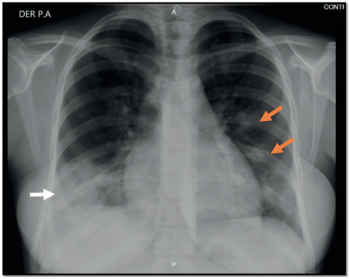

Mujer de 24 años de raza mestiza, procedente del municipio de Soledad, Atlántico, quien se dedica a labores del hogar. Consulta de urgencias por cuatro semanas de evolución con fiebre de patrón intermitente, asociado a tos húmeda con expectoración purulenta, dolor pleurítico derecho y disnea de esfuerzo que progresa hasta el reposo. Antecedentes de puerperio tardío de 37 días por parto vaginal (28/08/2019), con producto a término, con peso adecuado al nacer sin complicaciones. Cinco días previos a la consulta estuvo hospitalizada por la misma sintomatología actual y recibió terapia antimicrobiana parenteral; sin embargo, solicitó el retiro voluntario de dicha institución. Ingresó a una clínica de la ciudad de Barranquilla, con taquicardia, taquipnea y temperatura de 38,9 °C. En la exploración física se halló hipoventilación en bases pulmonares, crépitos generalizados con predominio basal derecho y sibilancias espiratorias ocasionales. En la analítica sanguínea presentó hemograma con leucocitosis y neutrofilia, anemia grado 3 OMS y elevación de reactantes de fase aguda (leucocitos: 22.090 x103/mm3, neutrófilos: 88,4 %, hemoglobina: 6,6 gr/dl, VCM: 81,7 dL., HCM: 26,3 pg., plaquetas: 188.000 x103/mm3, proteína C reactiva cuantitativa: 314 mg/L, VSG: 100 mm/hora, creatinina: 0,53 mg/dl), radiografía de tórax (figura 1). Con consolidado basal derecho y opacidades alveolares con distribución multilobar de predominio en hemitórax izquierdo, TC de tórax (figura 2). Con áreas de consolidación en base derecha, nódulos múltiples con distribución predominante peribroncovascular, algunos de ellos cavitados, adenopatías mediastinales. Se inició tratamiento antimicrobiano con piperacilina tazobactam más claritromicina y transfusión de hemoderivados y estudios de extensión. La valora el Servicio de Neumología, que en el diagnóstico diferencial considera neumonía bacteriana, micosis, micobacterias, enfermedades granulomatosas y malignidad. Los exámenes de control documentaron baciloscopia seriada. No se observan BAAR en 100 campos microscópicos. Anticuerpos para VIH: egativo, anticuerpos antinucleares: negativo, P-ANCA: negativo, C-ANCA negativo, complemento C3: 100 mg/dl (normal), complemento C4: 12 mg/dl (normal), gases de arteriales sin alteración del ácido base o trastorno de la oxigenación. PCR para Mycobacterium Tuberculosis (GeneXpert MYB-RIF) en muestra de esputo: negativo, hemocultivos negativos a los cinco días de incubación. TC de senos paranasales: normal. Por presentar deterioro clínico requirió ingreso a la Unidad de Cuidados Intensivos. Se inicia terapia tetraconjugada con RHZE por sospecha para Mycobacterium tuberculosis y se escalona terapia antimicrobiana con meropenem y vancomicina. El departamento de Cirugía del Tórax realiza videotoracoscopia en la que encuentra el pulmón atrapado. Se realiza decorticación pulmonar liberando el pulmón y lobectomía segmentaria del lóbulo inferior derecho. Se envía una muestra para estudio histopatológico. Después del control de fuente y el manejo antimicrobiano, la paciente mejora su patrón respiratorio y se le da la alta médica, con la recomendación de continuar el tratamiento antituberculoso. El estudio histopatológico del espécimen de segmento pulmonar del LID documenta inflamación aguda y crónica severa, mediado por linfocitos y leucocitos polimorfonucleares, áreas de necrosis y formación de absceso, estudio negativo para granulomas o cambios malignos, aislamiento de Staphylococcus Aureus. Finalmente, se suspende el tratamiento tetraconjugado.

Tomografía computarizada de tórax